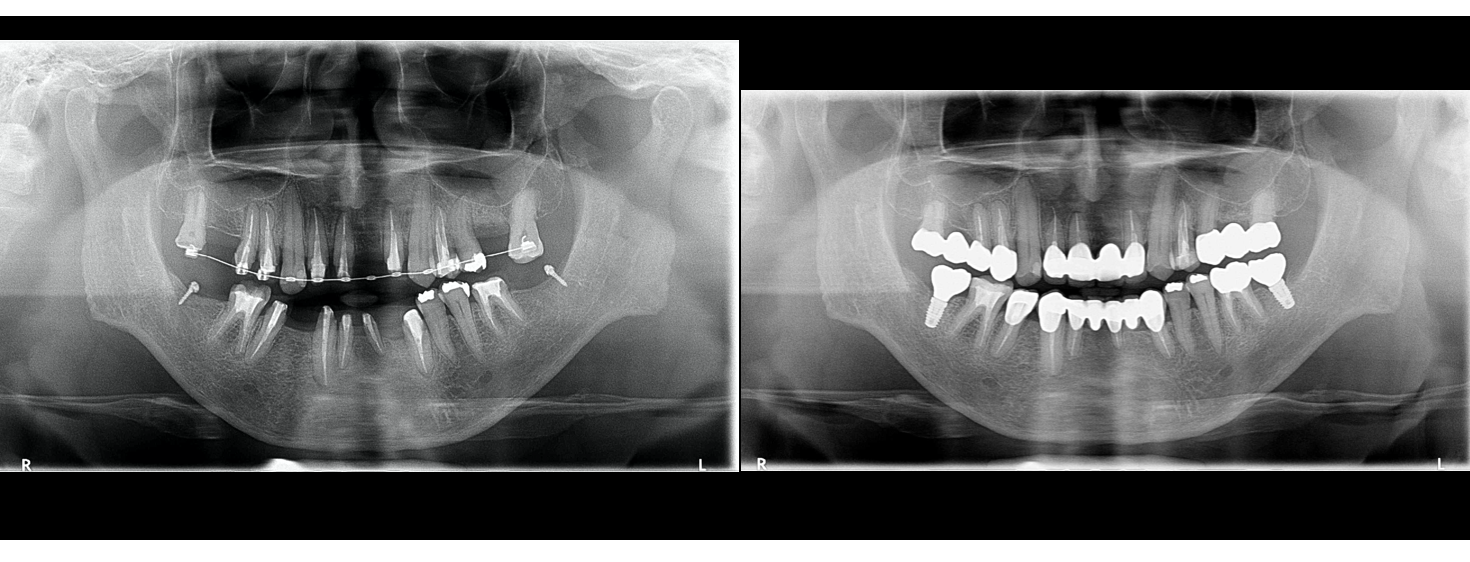

↑初診時のレントゲンを見てみましょう。局所的にかなり歯の周囲の骨が溶けているのがわかります。噛み合わせが原因の特異的な歯周病といえるでしょう。

術前術後のレントゲン評価です。よ〜くみてください、違いがおわかりになりますか?

術後のレントゲンです。

下顎最奥歯には左右1本づつのインプラントをお入れし、よりしっかりかめる状態にしました。

インプラントは歯を失った場所への最終最強治療手段であることは間違いありません!でも数はなるべく少ない方が良いですね、というのが25年インプラントをしてきた臨床医の私見です。